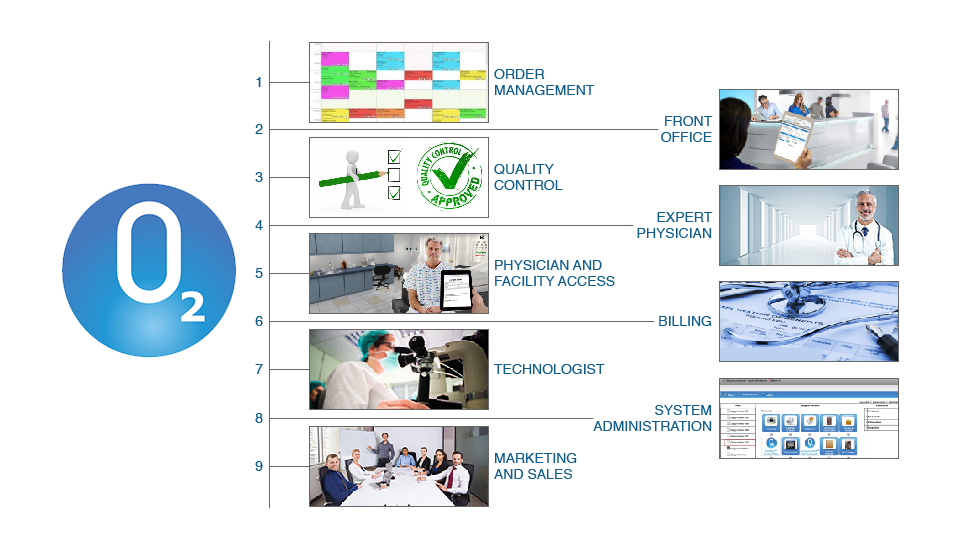

State-of-the-art End-to-end Solution

OXYGEN™ covers all aspects of diagnostic operations including patient scheduling and registration, Front Office management, Technologist operations, Marketing & Sales, Clinical Reporting, Quality Control, IT and Medical Billing. We have packed several state-of-the-art tools to make it easy for the Hospital and Diagnostic Center to collaborate with other healthcare providers and run their operations efficiently and profitably.